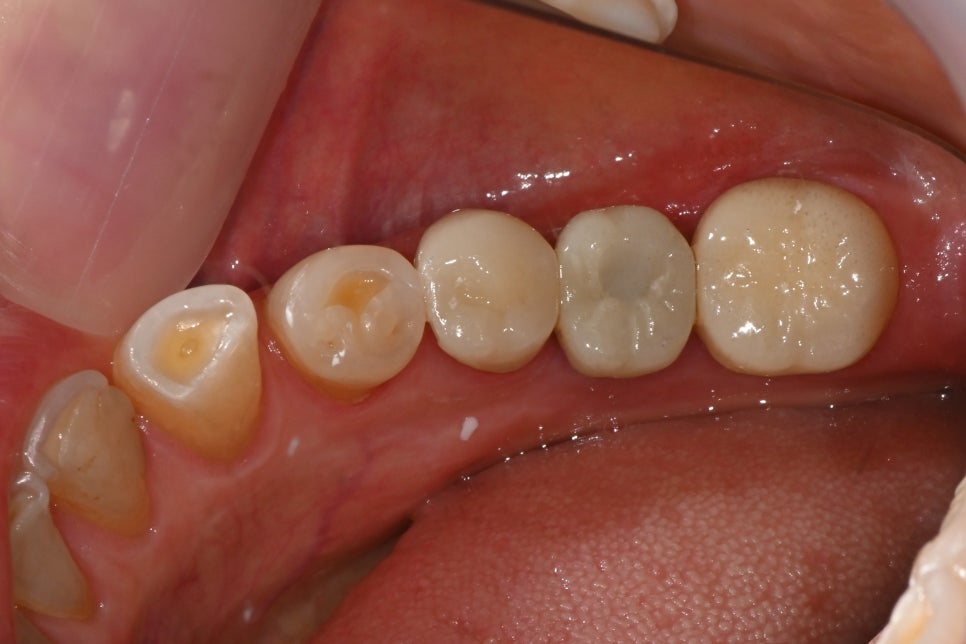

➤ 치료 마무리 사진

어금니 부위에 임플란트를 식립한 후, 크라운까지 셋팅이 완료된 모습입니다. 자연치와 조화로운 색상과 형태로 기능과 심미성을 동시에 회복했습니다.

어금니 임플란트 식립 및 보철물 완성 후 구강 내 사진

"자연치처럼 조화롭고 심미적으로 완성된 앞니 크라운과 기능을 회복한 임플란트 보철 모습입니다."